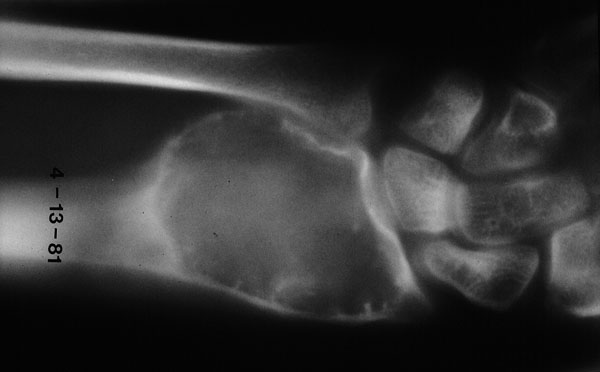

Giant cell tumor of bone

Giant cell

tumor

of bone in the distal radius of a 38 year old female. X-ray shows an expansile, radiolucent lesion arising in the

epiphysis

.